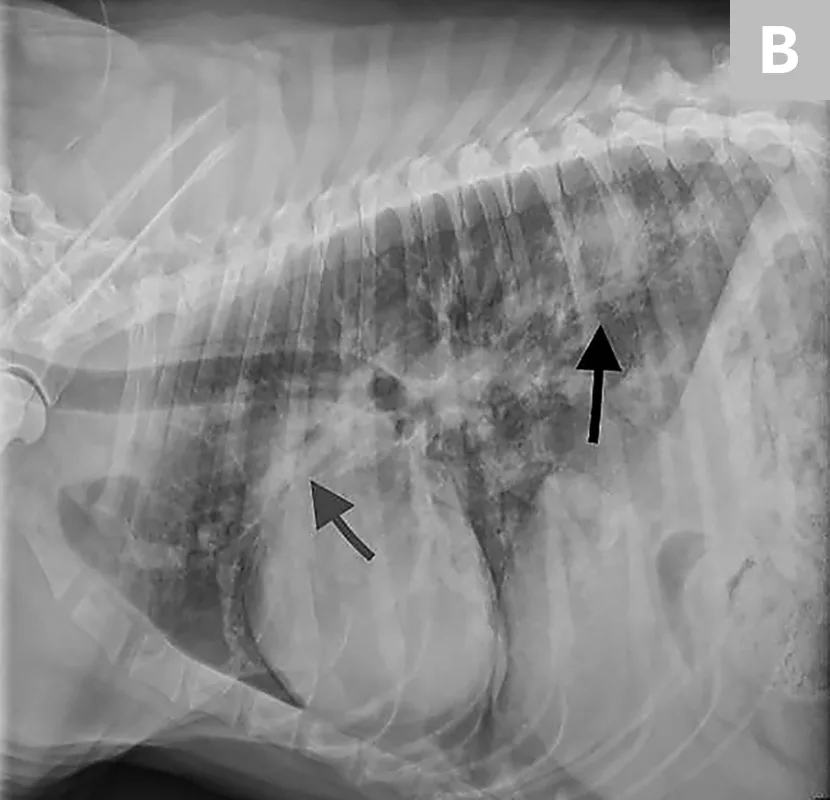

Thoracic radiograph of dog with lung and cardiac changes due to severe heartworm disease.

Radiograph from a dog with severe heartworm disease illustrating severe pulmonary arterial dilation, right heart enlargement, diffuse bronchointerstitial infiltrate, and focal region of pulmonary consolidation from embolized heartworms

FIGURE 1

Radiographs before (A) and 11 days after (B) melarsomine injection showing increased overall pulmonary infiltrate with focal region of pulmonary consolidation from embolized worms (black arrow). A progressive increase in cranial pulmonary artery size can be seen (gray arrow). Images courtesy of Clarke E. Atkins, DVM, DACVIM